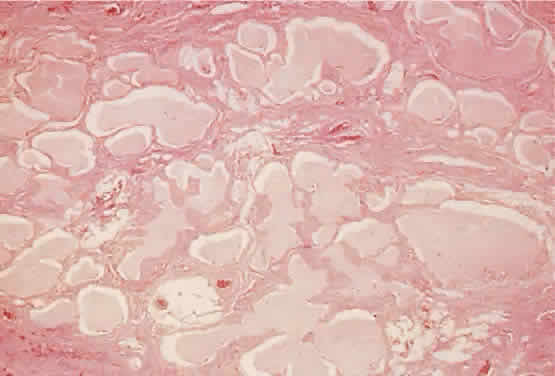

of capillary hemangioma evolves with its natural history. At initial

presentation, the lesion consists of lobular proliferations of plump endothelial

cells that circumscribe small vascular spaces (Fig. 10). Electron microscopy shows pericytes about the endothelial cells, but

smooth muscle is lacking.69 Involuted lesions show diminished endothelial cellularity and islands

of fibrofatty infiltration.61  Fig. 10. A capillary hemangioma consists of sheets of plump endothelial cells that

surround small blood-filled channels (hematoxylin-eosin; × 96). Fig. 10. A capillary hemangioma consists of sheets of plump endothelial cells that

surround small blood-filled channels (hematoxylin-eosin; × 96).

and bilateral vision loss.77,78 When the tumor's histology (see Fig. 10) and hemodynamic continuity are considered, it would seem that any intralesional